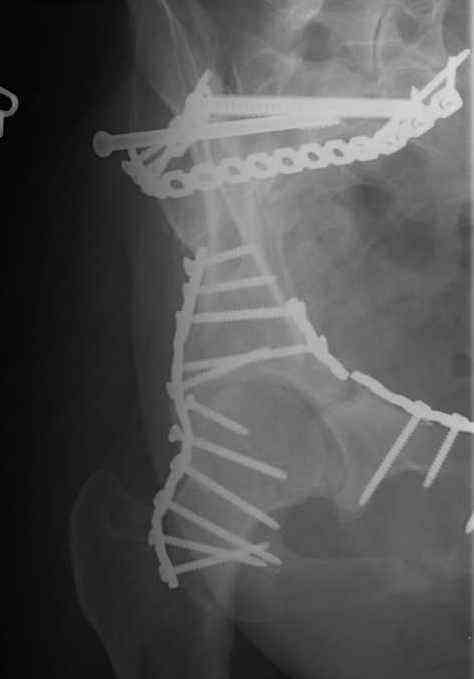

Looking for advice. This is a 48 yo non-smoking female s/p MCC 10 months ago. I do not have the initial injury films. She underwent ORIF as shown on attached file. She is having continued pain in low back/sacral region. Worse with sitting and prolonged walking. Has had pain since surgery. All of her wounds have healed uneventfully. Also has right hip pain laterally. No groin pain. Not aggravated with ROM of the hip. Infection work-up has been negative.

Any thoughts on the broken plate on the pelvic brim and the non-union on the anterior column. Doesn't seem like she's have pain from there.

Thank you...it might help to remove the disengaged and other iliosacral screws then insert longer lag screws into the upper sacral segment and if anatomically feasible into the second sacral segment as well.

You could do it percutaneously and even add an electrical stimulation device if that seems reasonable.

At this point, I'd ignore the right pubic root issue if asymptomatic.

If simple measures such as those above fail, then you could remove it all, take down the sacral fracture site, refix with alternate techniques, and bone graft.